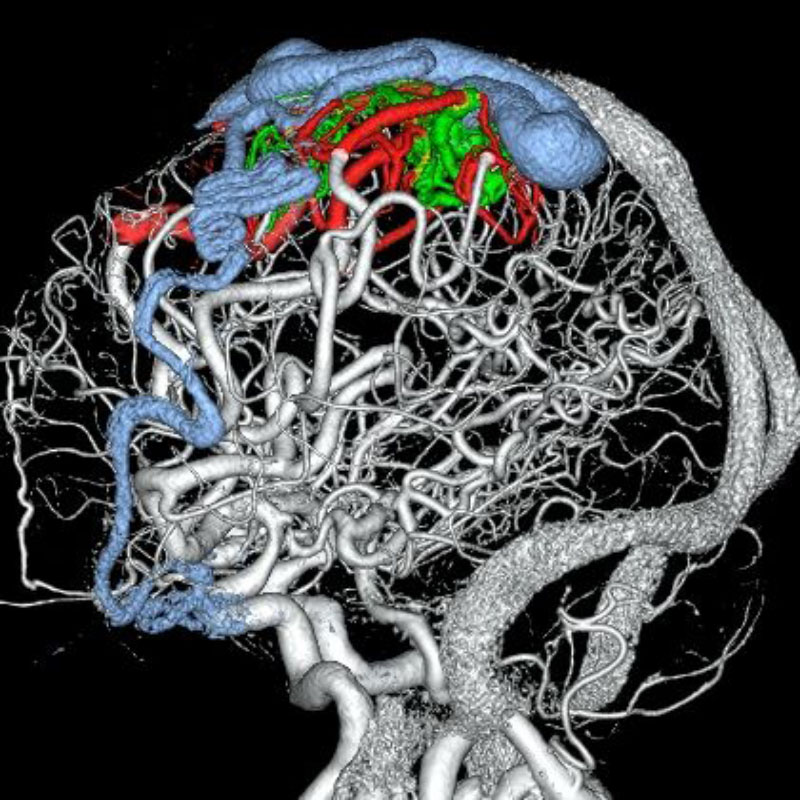

脳動静脈奇形

摘出術

南田/野本/古谷/元永